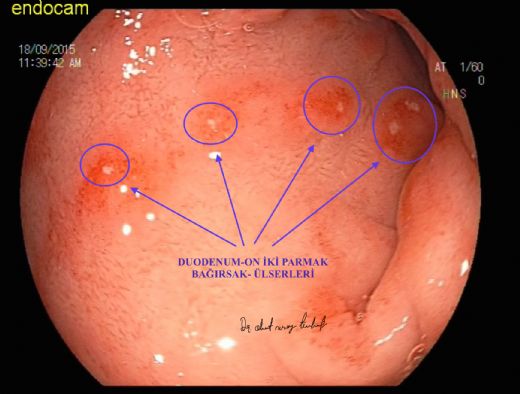

Oniki Parmak Bağırsağı Ülseri: Belirtileri ve Tedavisi On iki parmak bağırsağı ülseri, duodenum olarak bilinen on iki parmak bağırsağının iç yüzeyinde oluşan yaralardır. Bu ülserler, genellikle mide asidinin aşırı üretimi veya Helicobacter pylori adı verilen bir bakterinin varlığı ile ilişkilidir. On iki parmak bağırsağı ülserleri, sindirim sistemi bozuklukları arasında yaygın bir durumdur ve hem erkeklerde hem de kadınlarda görülebilir. Oniki Parmak Bağırsağı Ülserinin Belirtileri On iki parmak bağırsağı ülserinin birçok belirtisi vardır. Bu belirtiler kişiden kişiye değişiklik gösterebilir, ancak en yaygın olanları şunlardır:

Bu faktörlerin varlığı, on iki parmak bağırsağı ülseri gelişimini tetikleyebilir veya mevcut ülserin kötüleşmesine yol açabilir. Oniki Parmak Bağırsağı Ülserinin Tanısı On iki parmak bağırsağı ülserinin tanısı genellikle aşağıdaki yöntemlerle konulur:

Endoskopi ile tanı konulabileceği doğrudur. Bu işlemde, ince bir tüp üzerine yerleştirilmiş bir kamera ağızdan sokularak yemek borusu, mide ve onikiparmak bağırsağı incelenir. Genellikle lokal anestezi ve bazen hafif bir sedasyon uygulanarak yapılır. Bu sayede, doktorunuz sindirim sisteminizdeki sorunları daha net bir şekilde gözlemleyebilir.